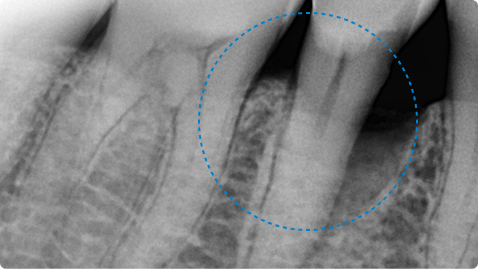

01

오랜 잇몸병으로 발치 직전의 치아, 잇몸 재생 치료로 자연치아 유지

치료 전

치료 후

치료 내용

• 좁고 깊은 치주낭(잇몸 주머니), 염증과 치아 흔들림, 타 치과에서 발치 권유

• 치주수술 + 엠도게인 적용으로 잇몸과 잇몸뼈 재생 유도

• 치료 후 치주낭 깊이 감소, 잇몸 회복 및 흔들림 안정